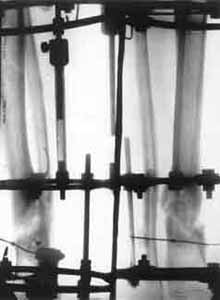

False joint of lower/third of shinbone.

Osteosynthesis with elimination of deformations and electrostimulation(period of treatment - 3 monthes). Osteosynthesis with elimination of deformations and electrostimulation(period of treatment - 3 monthes).

Osteosynthesis with elimination of deformations and electrostimulation (period of treatment - 3 monthes).